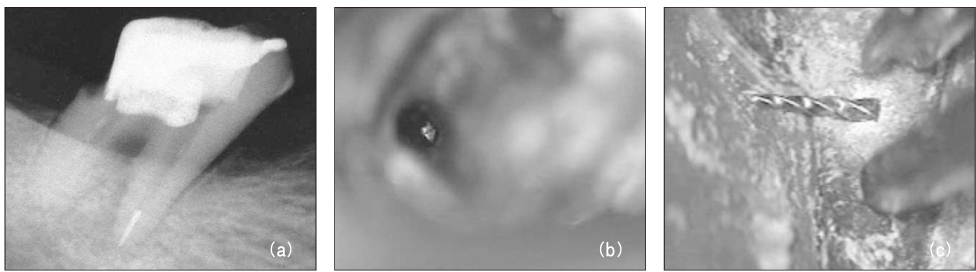

Figure 1

Diagnostic intraoral radiograph (a). Separated file in the mesial root isthmus (b, c) and remove it using ultrasonic device under microscope (d).

Figure 1 Diagnostic intraoral radiograph (a). Separated file in the mesial root isthmus (b, c) and remove it using ultrasonic device under microscope (d).